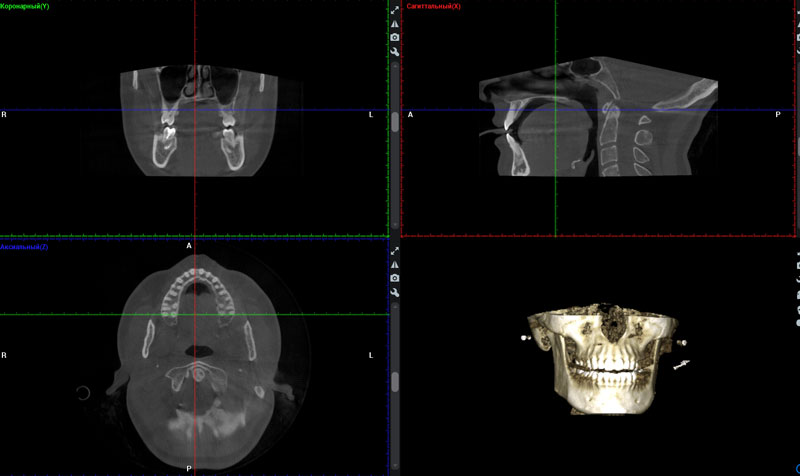

Спектр рентгенодиагностических услуг в нашей клинике широк – от прицельного снимка одного зуба, ортопантомограммы, до объёмного 3Д исследования смежных областей (височно-нижнечелюстные суставы, кости лица и черепа, верхнечелюстные ( Гайморовы ) пазухи.

| 3D КЛКТ (запись на CD)/одна челюсть | 1200 |

| 3D КЛКТ (запись на CD)/две челюсти | 1900 |

| 3D КЛКТ (запись на CD)/две челюсти + гайморовые пазухи | 2900 |

| 3D КЛКТ 1 объем (3 единицы) | 800 |

Обращаем ваше внимание - диагностика стоматологических заболеваний в нашей клинике производится с использованием высокоточного рентгеновского аппарата PLANMECA ProMax 3D Plus, что позволяет получить трехмерное цифровое изображение для тщательного изучения клинической ситуации при низкой лучевой нагрузке пациента.

С помощью рентгена врач может увидеть состояние каждого зуба и его корней, рядом расположенные органы и ткани. Процедура помогает поставить правильный диагноз перед началом лечения и позволяет оценить качество работы стоматолога во время лечения и после его окончания, что очень важно при пломбировании каналов, удалении зубов, установке имплантатов.